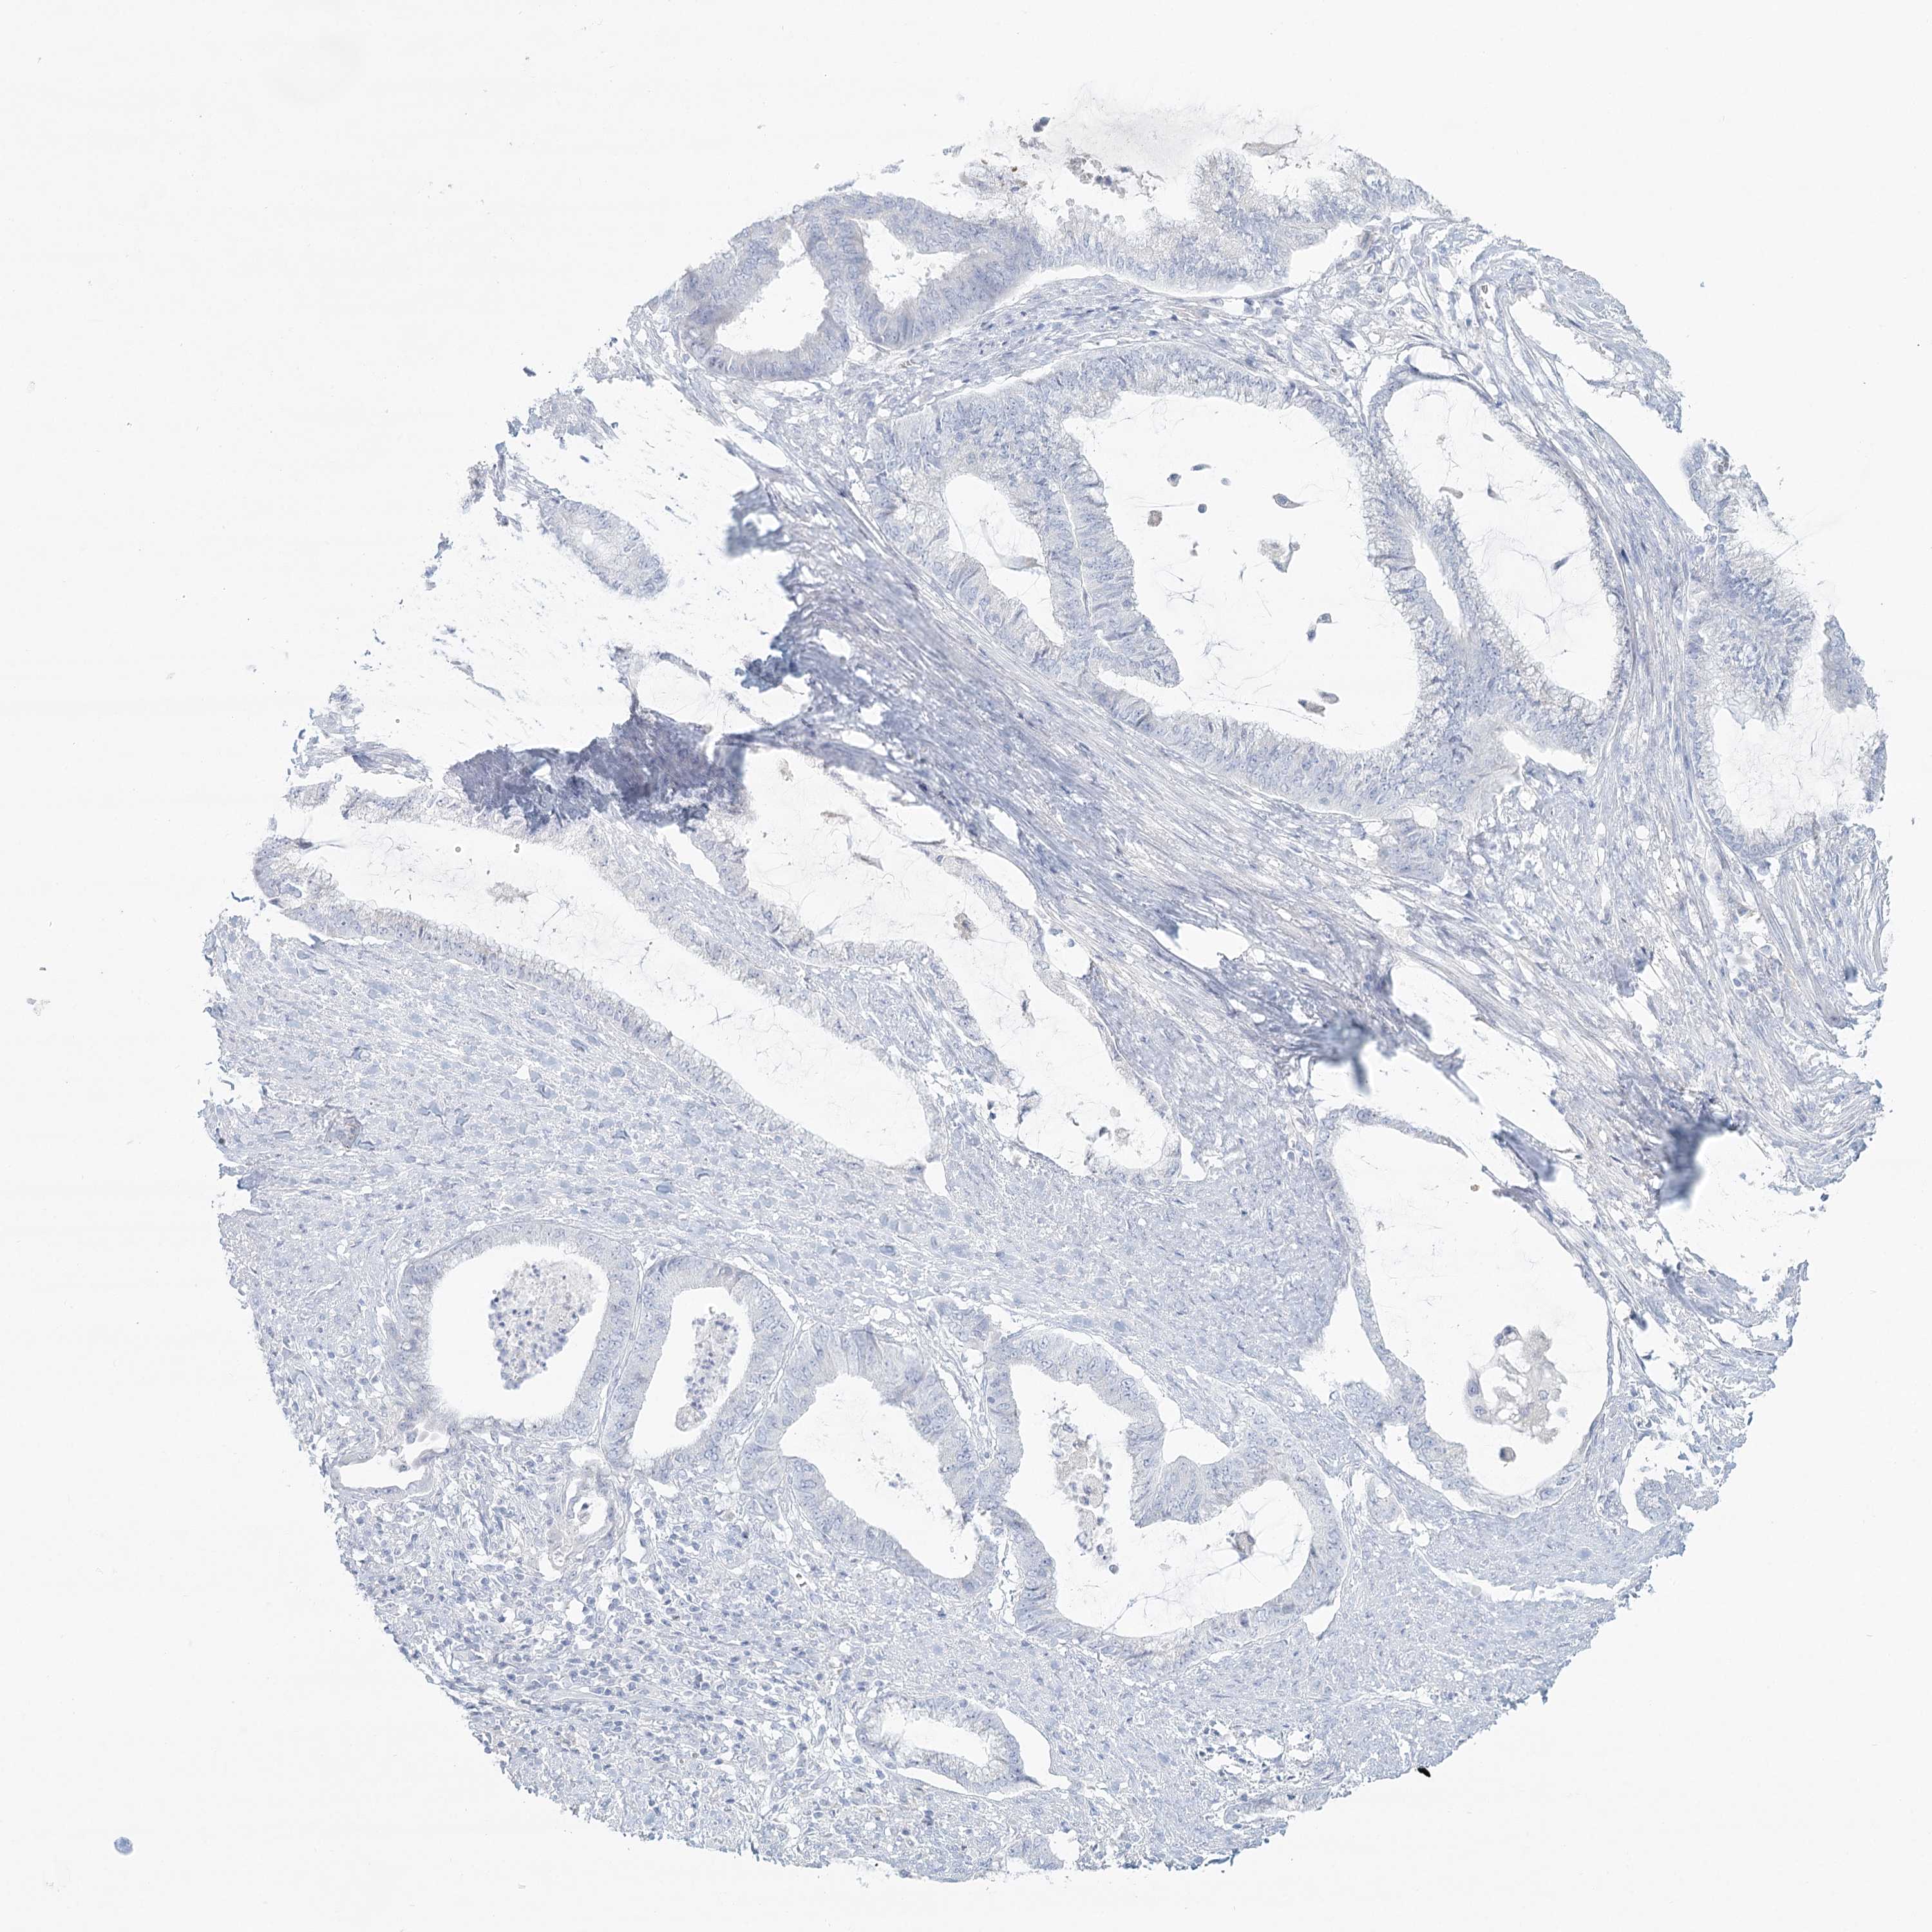

ENDOMETRIAL CANCER - Protein expressioni

A mouse-over function shows sample information and annotation data. Click on an image to view it in a full screen mode. Samples can be filtered based on level of antibody staining by selecting one or several of the following categories: high, medium, low and not detected. The assay and annotation is described here.

Note that samples used for immunohistochemistry by the Human Protein Atlas do not correspond to samples in the TCGA dataset.

Antibody stainingi

Antibody staining in the annotated cell types in the current human tissue is reported as not detected, low, medium, or high, based on conventional immunohistochemistry profiling in selected tissues. This score is based on the combination of the staining intensity and fraction of stained cells.

Each image is clickable and will lead to virtual microscopy that enables deeper exploration of all samples and also displays staining intensity scores, fraction scores and subcellular localization as well as patient and tissue information for each sample.

Antibody HPA036441

Antibody HPA036442

Staining

High

Medium

Low

Not detected

Intensity

Strong

Moderate

Weak

Negative

Quantity

>75%

75%-25%

<25%

None

Location

Nuclear

Cytoplasmic/membranous

Cytoplasmic/membranous,nuclear

Adenocarcinoma, NOS

Adenoma, NOS